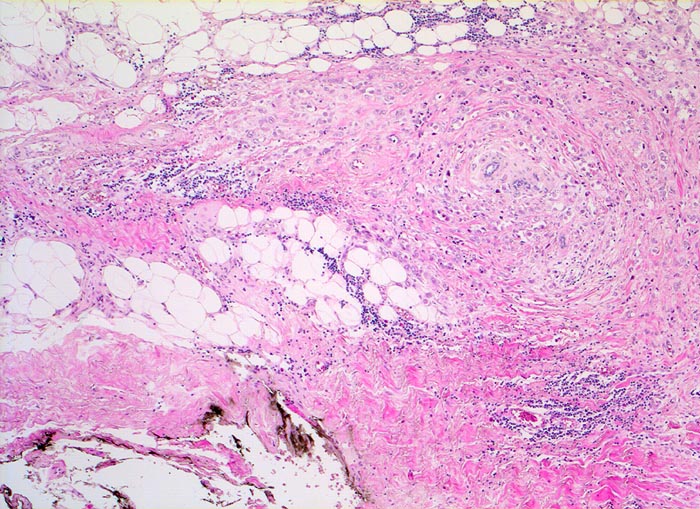

Invasiv lobuläre Karzinome sind in bis zu 80% mit einem lobulären in situ Karzinom und in 36% der Fälle mit einem duktalen Karzinom (in situ oder invasiv) assoziiert. Ein Viertel der Tumoren wächst multizentrisch. Das klassische invasive lobuläre Karzinom besteht aus kleinzelligen monomorphen Infiltraten, welche anstelle von Drüsen einreihige Tumorzellstränge bilden. Diese wachsen zirkulär um vorbestehende Drüsenläppchen (> 4221)und durchsetzen den Drüsenkörper diffus. Oft lassen sich intrazelluläre muzinhaltige Zytoplasmavakuolen nachweisen, die wie Siegelringzellen (> 4224) imponieren. Die Tumorzellen induzieren eine ausgeprägte desmoplastische Bindegewebsvermehrung.

Morphologische Merkmale:

• Multifokale Infiltrate eines invasiv lobulären Mammakarzinoms: Kleine monomorphe, zytoplasmaarme Tumorzellen bilden einreihige Ketten (gänsemarschartig = Indian files) oder sind konzentrisch um nicht neoplastische Drüsen angeordnet.

• Das Karzinom bildet keine Drüsen.

• Zytologisch blande Tumorzellen mit kleinen runden hellen Kernen.

• Reichlich dichtes desmoplastisches Tumorstroma.

• Lobuläre Neoplasie (=nicht invasiver intralobulärer Karzinomanteil): Neben den zystisch erweiterten Drüsen finden sich Mammaläppchen, deren Azini teilweise leicht vergrössert sind durch Ansammlungen von atypischen Zellen mit vergrösserten Kernen und prominenten Nukleolen. Die Basalmembran der tumorbefallen Azini ist erhalten.

• Nich neoplastisches Mammaparenchym mit Fibrose, erweiterten Gängen ausgekleidet von metaplastischem apokrinem Epithel.